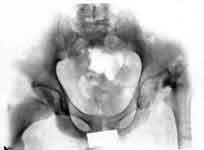

3.После удлинения бедра.

4.Результаты лечения.